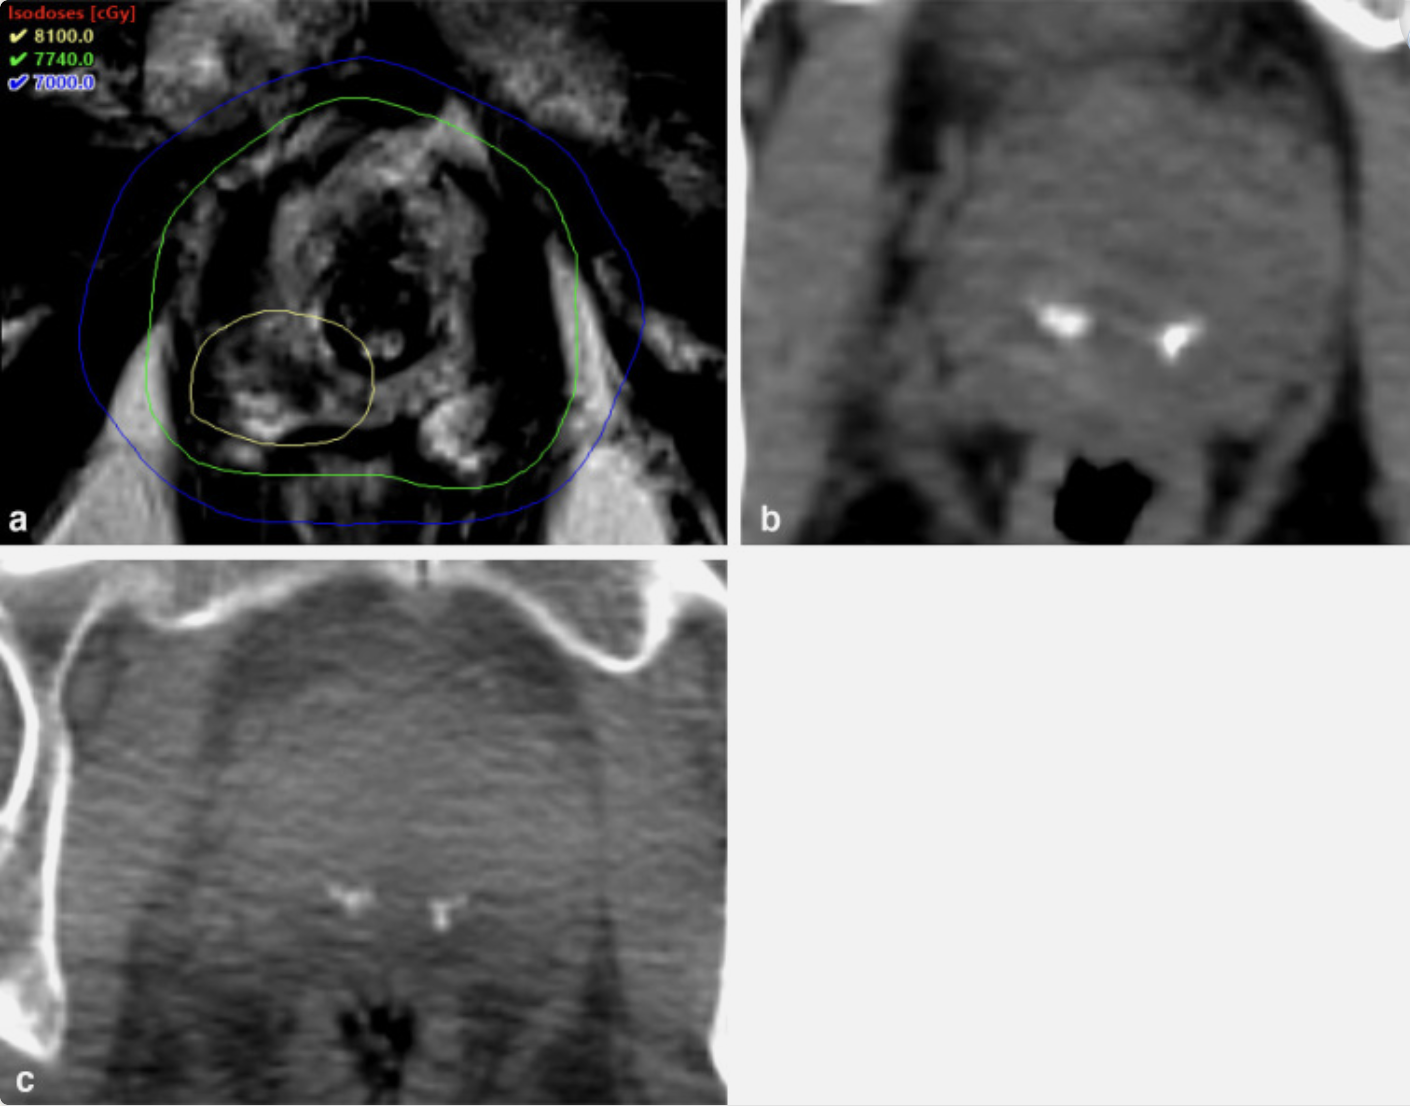

Head and neck MRI showing IMRT isodose distributions

MRI displaying highly conformal intensity-modulated radiation therapy (IMRT) isodose distributions for a complex head and neck cancer, sparing critical normal tissues.